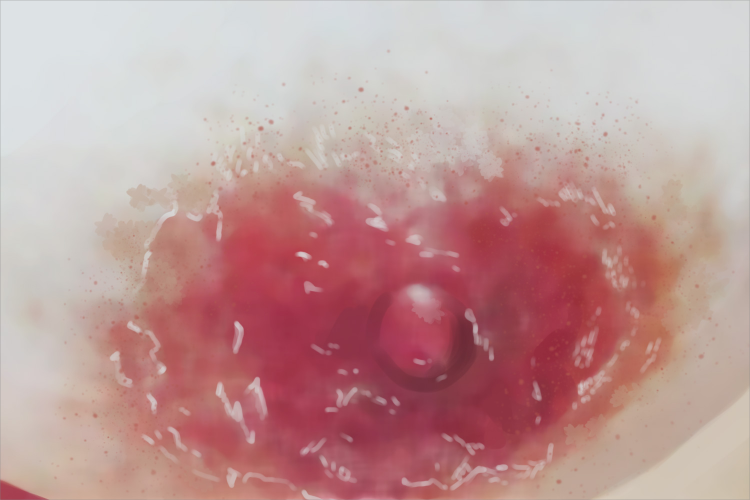

乳房Paget病可见有糜烂,边界清楚,稍隆起,乳头回缩,有渗液,使局部看起来湿润,露出鲜红色基底部,可有瘙痒感。